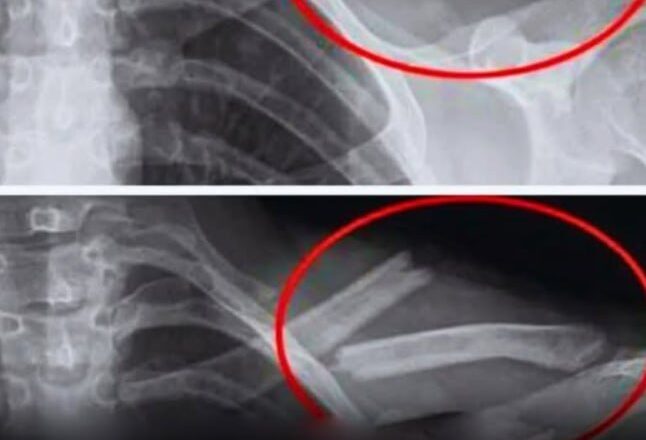

Однак цей популярний напій може непомітно атакувати ваші кістки, роблячи їх більш схильними до пошкоджень.

Дослідження показують, що надмірне вживання газованої води призводить до зниження щільності кісток, особливо у жінок. Іншими словами, ваші кістки слабшають… іноді без жодних симптомів, аж до перелому.

Дослідження, проведене в США за участю 2500 жінок, показало, що ті, хто регулярно пив колу, мали нижчу щільність кісток у стегнах. І вони робили це несвідомо.

Дослідження, проведене серед дівчат-підлітків, також виявило зв’язок між споживанням газованих напоїв та підвищеним ризиком переломів.